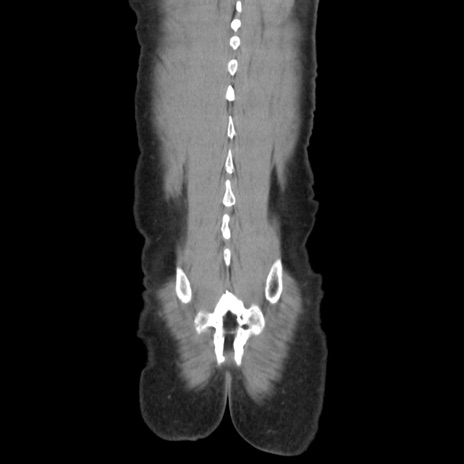

症例37(冠状断像)

【症例】40歳代 男性

【主訴】腹痛

【現病歴】4時間ほど前に電車に乗車中に臍部上より腹痛出現。徐々に増悪し起立困難となり、救急外来受診。生ものは数日食べていない。今朝お雑煮を食べた。

【身体所見】BT 36.8℃、BP 117/84mmHg、HR 91/min、SpO2 97%、苦悶様、腹部:臍上部広範囲圧痛あり、反跳痛±

【データ】WBC 8100、CRP 0.03